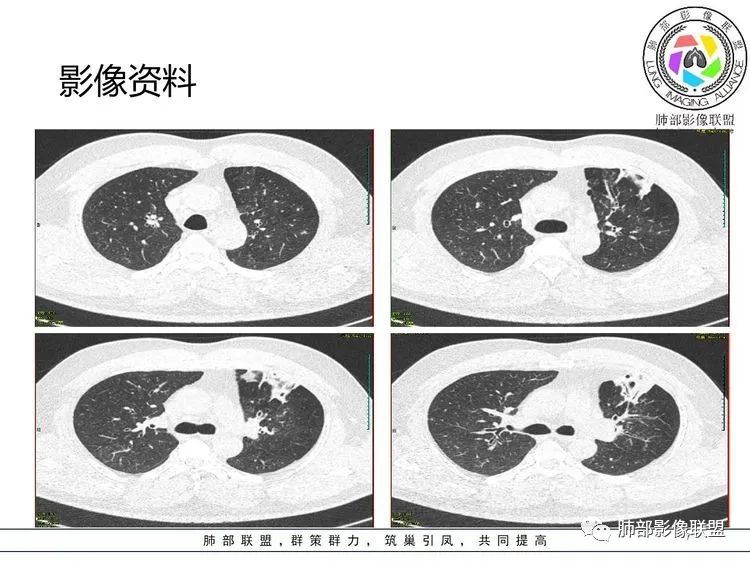

张延军: 左肺上叶前段沿支气管束周围见实变影,边缘收缩,界不清,内见小空洞影,与支气管相通,病变周围散在结节及斑片状高密度影,树芽征(+),中年男性,类似结核中毒症状,感染指标升高,考虑NTM,结核代排。

joyzhy:中年男性,咳嗽咳痰,炎性指标升高。影像,左肺上叶片状实变,部分平直,部分内收,支气管血管束增厚,头孢类治疗后效果不佳。考虑非典型肺炎,支原体?鉴别:吸入性肺炎

衡妈: 实变+支气管充气征,可见支气管壁增厚,病灶边缘模糊磨玻璃。我没有看到树芽;NTM 一般要有背景 比如支扩

张丽红: 有发热,咳嗽呼吸道感染症状。左肺上叶斑片影,内部支气管走行自然。右肺也有散在斑片影。考虑非结核分枝杆菌,结核

青藤之凉: 支原体肺炎的影像特征相对比较明显。有支气管壁增厚、支气管扩张样改变、支气管充气征。小叶小结节,有点状或者斑片状的浸润影、有实变影,表现为树芽征、树雾气征。

影像学特点:①支气管壁增厚、支气管周围炎。②腺泡结节、树芽征、树雾征(见病例1)。③结节融合,大片实变,部分边缘收缩。④分布上较广泛 。